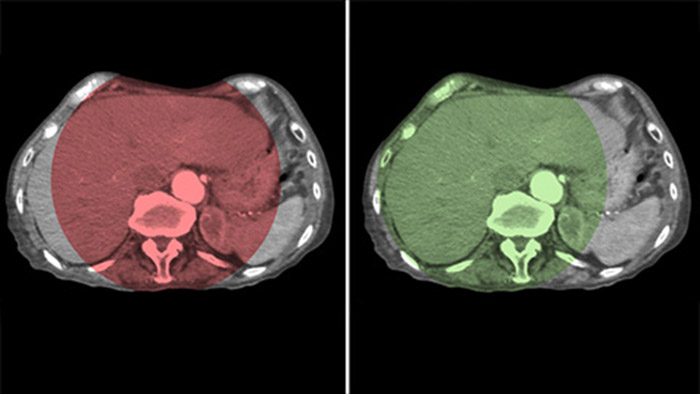

Optimización de la visualización de arterias y tumores con la THC Dual

Visualización óptima de arterias y tumores con la THC Dual

THC Dual permite la adquisición de imágenes en 3D de una fase arterial para visualizar estructuras vasculares y una posarterial (fase retardada) para ver la acumulación del medio de contraste, en un solo paso automático.5

Fusión de imágenes con Dual View

Dual View permite la visualización simultánea de dos conjuntos de datos de la THC. Tanto la fase arterial como la retrasada se pueden mostrar una al lado de la otra o en una sola vista de superposición fusionada.